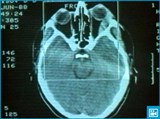

Рентгенологическое исследование основано на особом свойстве рентгеновских лучей проникать через плотные непрозрачные среды и поглощаться ими в неодинаковой степени в зависимости от их химического состава и физических свойств. В результате на светочувствительном экране, воспринимающем рентгеновские лучи, прошедшие через участок человеческого тела, получают плоское теневое позитивное изображение внутренних органов человека без нарушения целостности кожных покровов. Различные органы и ткани дают на экране тени неодинаковой интенсивности, что и создает возможность отличить их друг от друга. Например, на фоне прозрачных для рентгеновских лучей легких можно исследовать сердце (размеры, положение), определять воспалительные участки в легких и др. Особенно успешно прямое рентгенологическое исследование применяется при диагностике целостности костей скелета, т.к. костная ткань в наибольшей степени поглощает рентгеновские лучи и очень хорошо контрастируется на фоне остальных тканей человеческого тела.

В настоящее время для более детального исследования полых органов и трубчатых структур (желудок, кишечник, почки, сосуды и др.), дающих сравнительно однородную тень при прямом рентгенологическом исследовании, широко применяют рентгеноконтрастные методы: ангиография, урография. Так, при общем исследовании пищеварительного тракта больному дают выпить взвесь сульфата бария, непрозрачную для рентгеновских лучей. В результате на экране (или пленке) получают четкую картину верхних отделов желудочно-кишечного тракта, хорошо выявляющую его форму, очертания и положение.

При оценке рентгеновского снимка всегда следует помнить, что любая рентгенограмма нуждается в квалифицированном толковании. Врач, оценивающий снимок, должен хорошо знать топографическую анатомию человека, течение патологического процесса, механизм формирования рентгеновского изображения и многое другое. Поэтому не стоит самостоятельно ставить какой-либо диагноз по имеющемуся на руках снимку: специалист это сделает более грамотно.